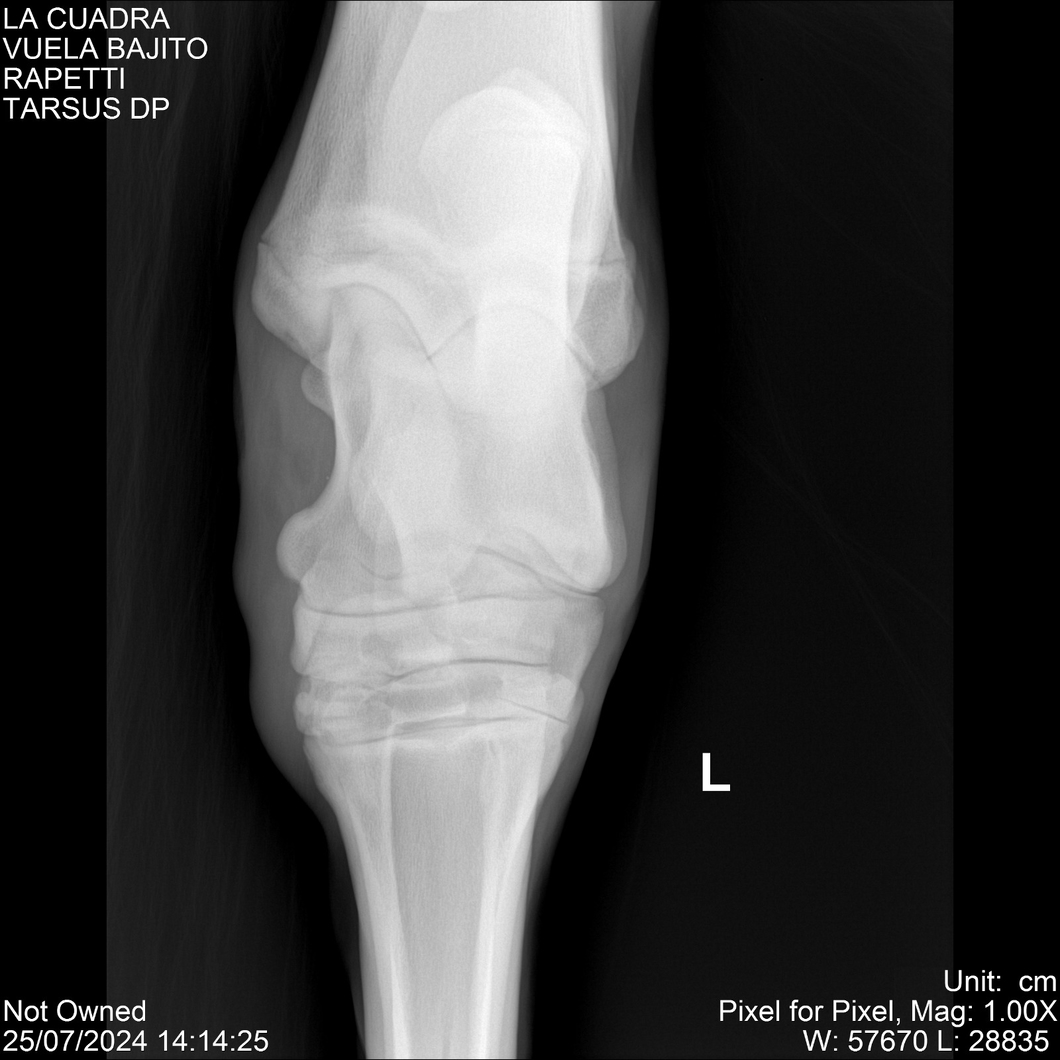

LOTE 16, VUELA BAJITO Lote Anterior Volver al remate Lote Siguiente Ficha Contacto Montevideo - Ficha del Lote Identificador: #284451 Categoría: Yeguarizos Montevideo - 77 Visualizaciones ClicData Contacto Empresa: Abelenda N. R., Walter Hugo Nombre*: Teléfono* : E-mail* : Mensaje Enviar Registrese gratis Este contenido Exclusivo está disponible sólo para usuarios registrados Ingresar